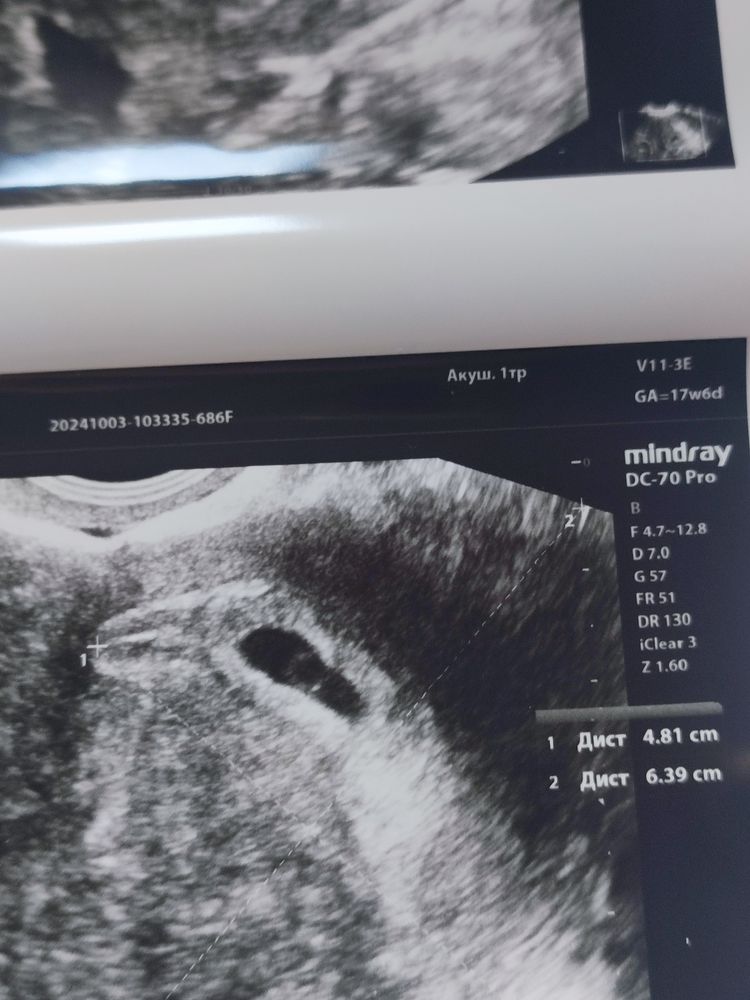

Жанна, у меня уже 4😂😂а срок всего 6 недель, хотя врач почему-то 5.2 по переносу ставит (я так и не поняла, почему)

УЗИ- контроль через 2,5 недели после чистки: Идем на крио! Второй Скрининг,20 недель,и 280 грамм счастья🥰